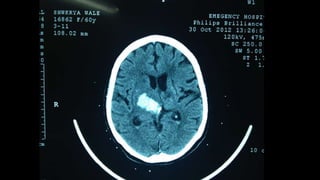

Hemiparesis with facial weakness: brain CT scan or brain MRI, with or

NB: Urgent non-contrast brain CT scan is the most suitable imaging

modality in patients with acute hemiparesis because of its availability in

Emergency Departments (usually), and it is rapid (the period of the test

is very brief (compared to MRI). Drawback: poor visualization of

posterior fossa structures because of boney artifacts, except in